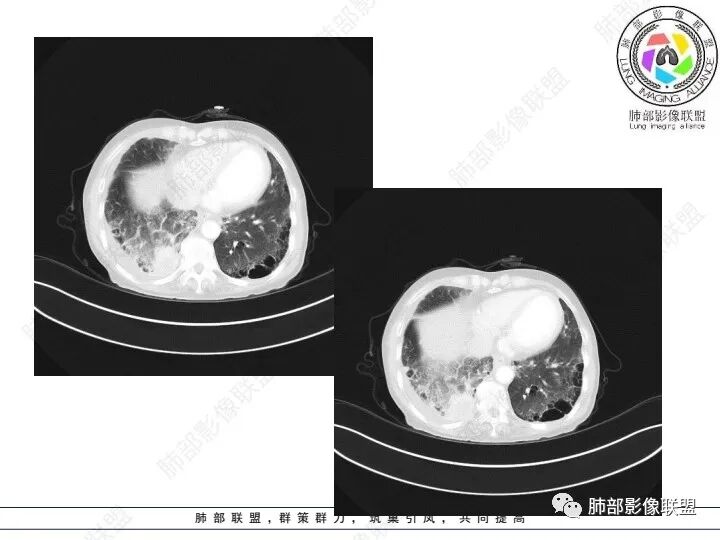

患者老年女性,腹痛、黑便4小时。查肿瘤结果CA125明显升高,余正常。胸部CT:双肺胸膜下间质性改变,右肺胸膜下多发结节灶,以右肺下叶为大,增强渐进性强化,内低密度灶。右肺门淋巴结肿大伴钙化,右中间支气管狭窄,右侧包裹性胸腔积液。综合考虑恶性,腺癌可能大。鉴别转移。

女,69,腹痛、便血4小时。CA125增高。胸部CT:肺气肿背景。右下叶不规则肿块影,处于外周气肿带与正常肺交界区,强化不均匀,中心有坏死;纵隔及肺门多发肿大淋巴结、融合,包绕支气管,部分钙化、环形强化;右下支气管周围管壁增厚伴环形钙化、狭窄。右侧胸膜多发结节灶,增强后明显强化,右侧胸腔积液。考虑恶性,右下肺腺Ca多发转移?转移瘤?鉴别TB、IgG4等。

3、胸部增强CT示右肺下叶脊柱旁不规则软组织肿块,侵及壁层胸膜外,密度不均匀,不均匀强化,中心低密区可疑坏死,右侧胸腔积液、胸膜结节影或结节样增厚,增强扫描可见强化,右侧肺门及纵隔内可见淋巴结肿大、融合,右侧中尖段支气管及右肺下叶支气管受侵,管腔狭窄。